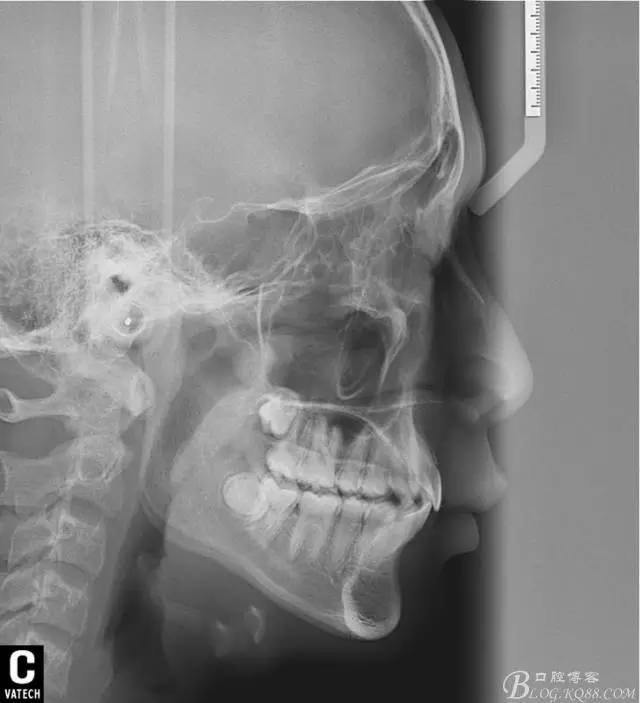

輔助診斷:由于當時條件有限,沒能拍攝全景,側(cè)位片,更不用說頭影測量數(shù)據(jù)來診斷了,只能憑借經(jīng)驗和些小技巧來判斷了,這類案例到底是患者所說的前突還是下合后縮。

術后全景,側(cè)位照。